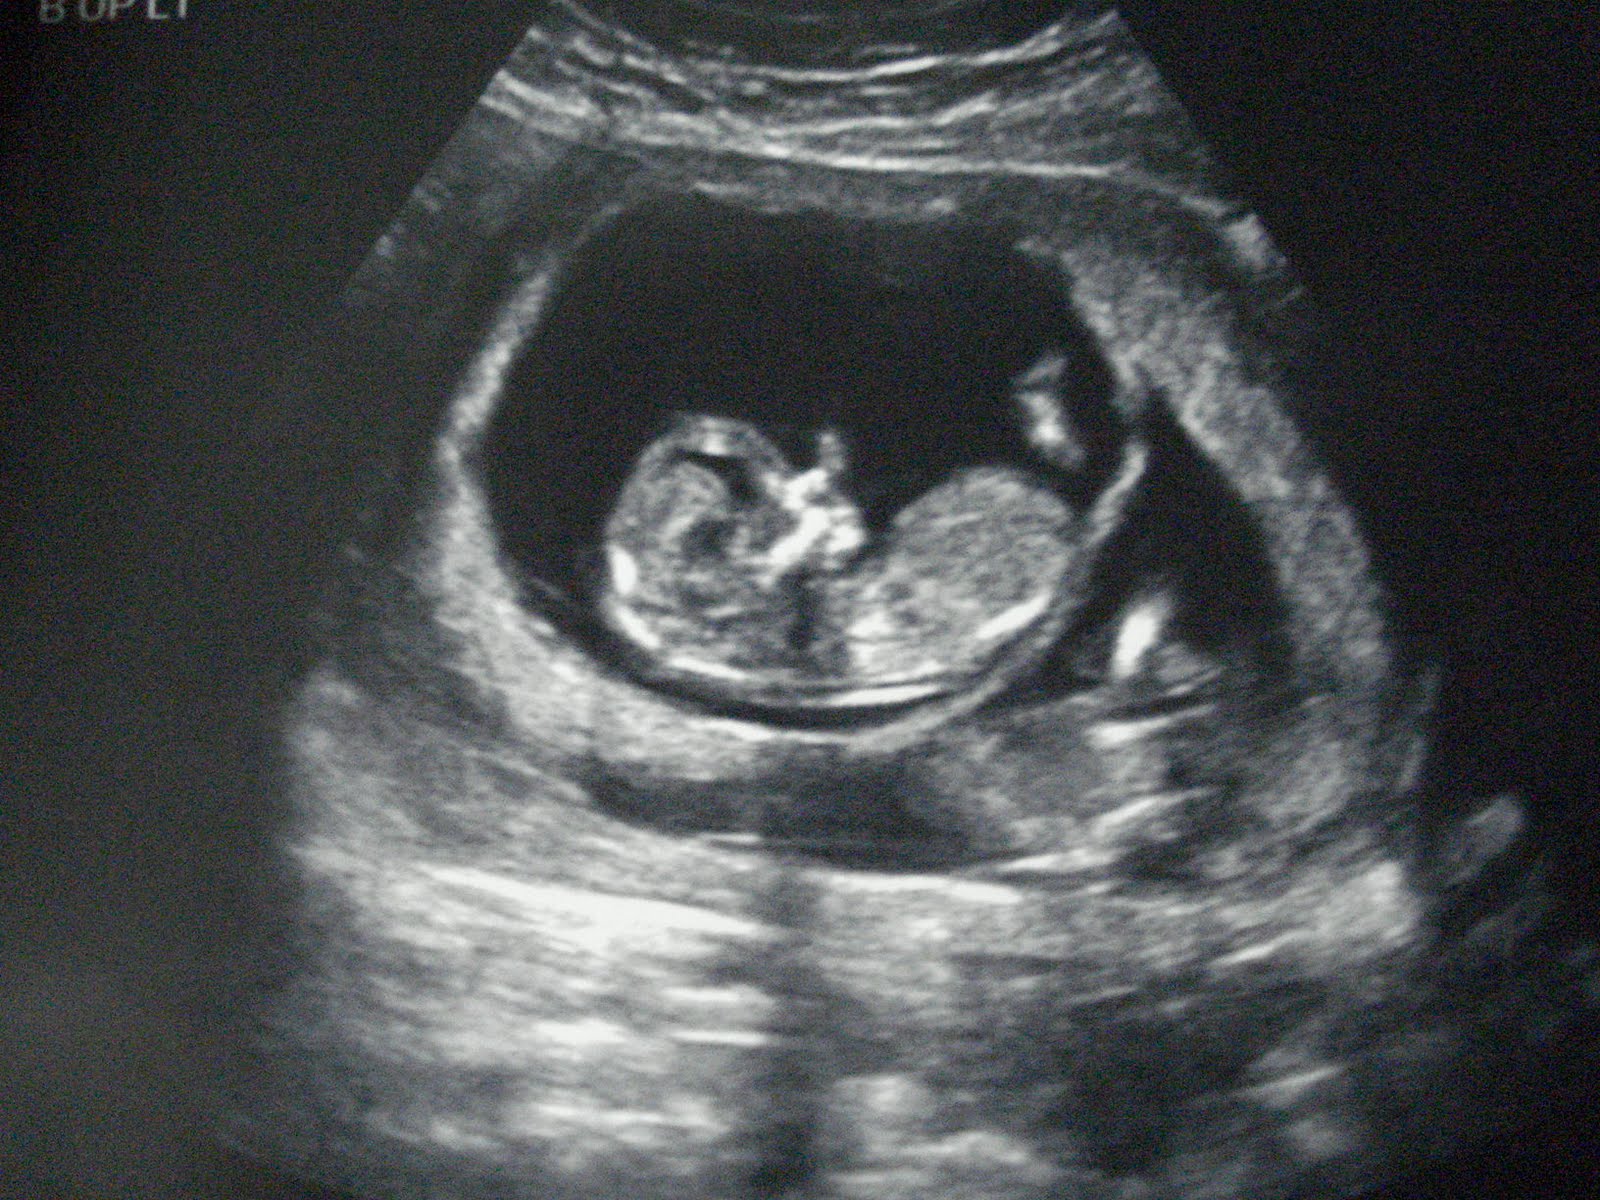

Hi everyone! My name is Heather, I am 29 & have been married to the love of my life, Pat, for two and a half years. We started trying to add to our family right away due to some of my health problems and now we are here on this blog keeping our family & friends up to date on our journey.

We are very blessed to have a great support system, lots of cheerleaders routing for us and great listeners when this road gets tough. Infertility is not for the weak, it is a long and tough road that I am hoping comes to an end very soon :)